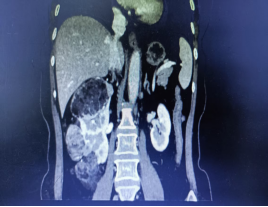

术前影像

年近6旬的张女士(化名),近期在常规体检中发现右肾存在占位性病变,进一步检查后确诊为右肾多发肿瘤:最小直径约1cm,最大直径约8cm!尽管术前检查考虑良性可能,但由于患者肾脏肿瘤多发,保肾难度大,且对侧肾功能良好,术前检查无禁忌症,医生最终为她实施了全麻下腹腔镜右肾切除手术,张女士(化名)遗憾地失去一颗宝贵的肾脏。